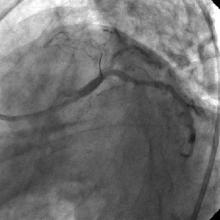

3) LAD: Ostial CTO ( Figure 2) with collaterals from RCA and LCX (Figure 3).